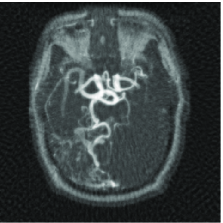

We mimic an MR experiment by taking our unknown image to be the pixel MR angiogram image shown in Figure 12(a). We sample the image along 80 lines in the Fourier domain (see Figure 12(b)), effectively taking real-valued measurements . In plain terms, we undersample by a factor of about 3.

Figure 12(c) shows the minimum energy reconstruction which solves

| (18) |

Figure 12(d) shows the result of TV minimization. The minimum -analysis (17) solution where is a three-scale redundant D4 wavelet dictionary that is times overcomplete, is shown on Figure 12(e). Figure 12(f) shows the result of reweighting the analysis with and set to 100. For a point of comparison, the maximum wavelet coefficient has amplitude 4020, and approximately 108000 coefficients (out of 655360) have amplitude greater than 100.

We can reinterpret these results by comparing the reconstruction quality to the best -term approximation to the image in a nonredundant wavelet dictionary. For example, an reconstruction error equivalent to the reconstruction of Figure 12(c) would require keeping the largest wavelet coefficients from the orthogonal wavelet transform of our test image. In this sense, the requisite oversampling factor can be thought of as being . Of course this can be substantially improved by encouraging sparsity, and the factor is reduced to using TV minimization, to using analysis, and to using reweighted analysis.

We would like to be clear about what this means. Consider the image in Figure 12(a) and its best -term wavelet approximation with ; that is, the approximation obtained by computing all the D4 wavelet coefficients and retaining the largest in the expansion of the object (and throwing out the others). Then we have shown that the image obtained by measuring real-valued Fourier measurements and solving the iterative reweighted analysis has just about the same accuracy. That is, the oversampling factor needed to obtain an image of the same quality as if one knew ahead of time the locations of the most significant pieces of information and their value, is just 3.